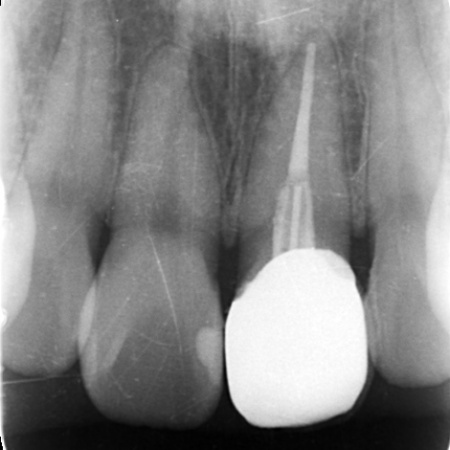

患者様は「できるだけ自分の歯のように自然な見た目にしてほしい」とご希望です。 そこで、白いグラスファイバーを用いた土台(ファイバーコア)に白い被せ物(ジルコニアセラミッククラウン)を装着する治療を提案し、同意いただきました。 ファイバーコアは光を通す素材のため自然な透明感があり、歯根への負担が少ないことが特徴です。 ジルコニアセラミッククラウンは、強度の高いジルコニアのフレームの上にセラミックを何層にも盛って焼き付けるレイヤリングを施した被せ物です。 治療初日は歯がないことで生じる不便さや見た目への影響に配慮し、その場で仮歯を作製して装着しました。 土台が完成したあとは歯科用顕微鏡のマイクロスコープで確認しながら、被せ物をスムーズに装着できるよう歯の形を丁寧に整えました。 その後、変形しにくいシリコン素材で精密な歯型を採取し、それをもとにジルコニアセラミッククラウンを作製しています。 |